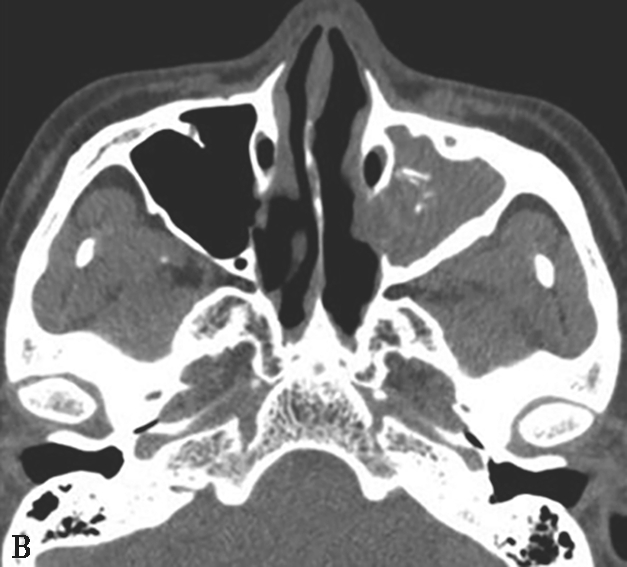

1.CT表现

该病多发生于上颌窦和筛窦,其次为蝶窦,额窦罕见。早期表现为单侧鼻腔、鼻窦黏膜和软组织增厚,但无特异性,应密切结合临床考虑;Silverman等提出上颌窦周围脂肪间隙软组织浸润为该病较早的征象;典型表现为鼻窦内充以软组织影,窦壁及邻近颅面部骨质可出现广泛骨质破坏,但无窦腔变形,窦腔内一般无钙化;广泛侵犯眼眶、颞下窝、翼腭窝、硬腭、颅面部软组织等邻近结构,严重者可侵犯颅内,出现脑膜炎、脑炎、脑脓肿、脑梗死等(图1-3-23A、B)。

2.MRI表现

T 1 WI多为低或等信号,T 2 WI多为高信号,增强后有明显强化。MRI能更清楚显示眼眶、颅内、海绵窦等鼻外蔓延范围,为治疗方案选择提供依据,对术后随访也有很大帮助(图1-3-23C~E)。